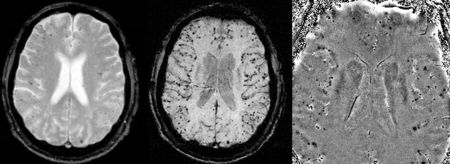

Susceptibility weighted imaging has been proposed as a tool for identifying CAA-related microhemorrhages.[17] Biopsies also play a role in diagnosing the condition.[18]